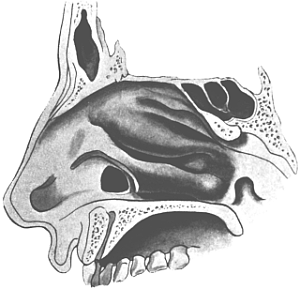

| 310. | Semi-diagrammatic Transverse Section of the Nose | 610 |